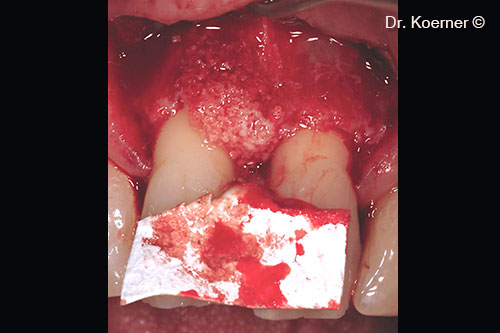

Rạch da theo kỹ thuật bảo tồn nhú lợi cải tiến

Nạo chân tóc bằng đầu kim cương Piezo

Lỗi được khắc phục bằng mp3® và màng Evolution được thiết kế riêng